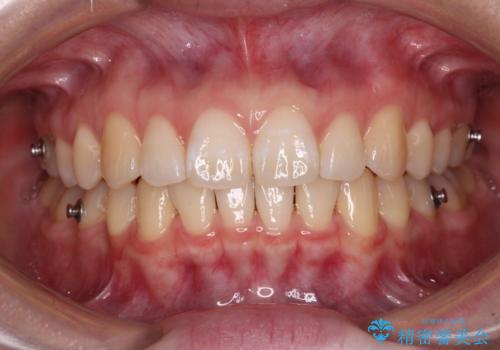

咬合高径の挙上により上顎前歯の突出感も改善することができ、整った口元となりました。